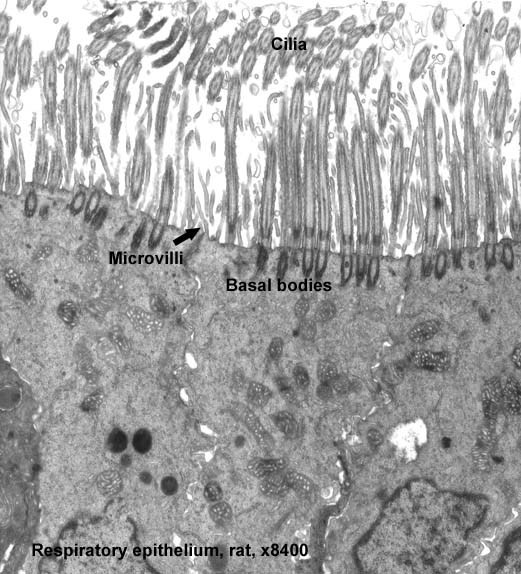

Respiratory Epithelium are made up of:

How would you classify respiratory epithelium?

pseudostratified columna

See respiratory epithelium: pseudostratidied columnar epithelium